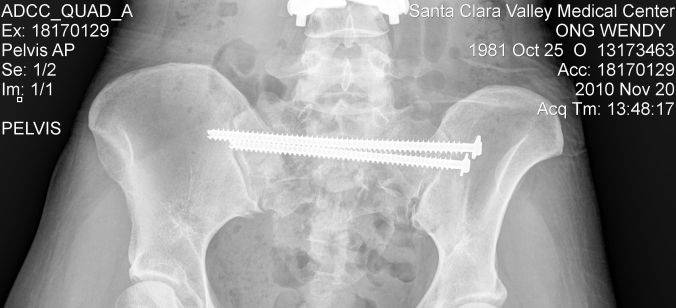

Another exciting medical event occurred when it turned out I had a raging bone infection (osteomyelitis) in my pelvis. Several symptoms presented themselves but I had no clue what the cause was. For example, I was eating about 4000-5000 calories a day and still staying under 100 pounds. I was also going hypoglycemic frequently, despite eating vast quantities of food. The hypoglycemia was bad in that it often hit me while I was skiing. I would lose my sense of balance and not even be able to make it down green or blue runs. Ski patrol was called out a few times to get me off the mountain. That was embarrassing. Initially, I thought it might be a thyroid issue but the results returned normal. It was only because I had decided to remove the steel rods in my pelvis because of some irritation I was experiencing that the surgeon discovered the osteomyelitis. A routine 30-minute procedure ended up taking several hours as he debrided the infected bone. If osteomyelitis progresses too far, amputation can sometimes be required, so it was fortunate they caught the infection when they did. My orthopaedic surgeon hypothesized that bacteria entered my body via the massive surgery to collect the pieces of my pelvis together (my climbing accident in 2010). Apparently, bacteria sitting on metal can lie dormant for a very long time before deciding to make their presence known. In my case, it was 8 years.